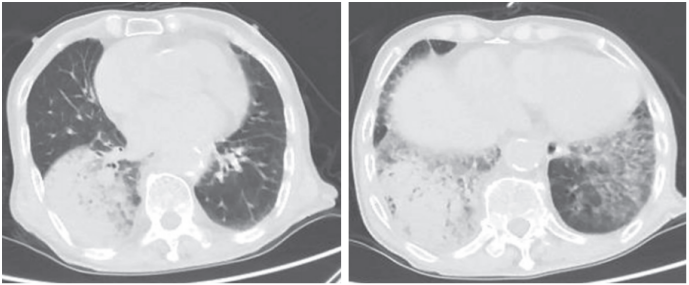

患者于2019年9月22日无明显诱因间断出现咳嗽、咳痰,黄黏液,量不多,不易咳出。于9月23日就诊我院急诊,入急诊后测体温最高为39.3℃。实验室检查:白细胞计数(WBC)为16.51×109/L,中性粒细胞(NEU)百分比为97.7%,白细胞介素-6(IL-6)>1520 pg/ml,快速降钙素原(PCT)检测为2~10 ng/ml,C反应蛋白(CRP)为308.2 mg/L。血气分析(普通面罩吸氧下):pH 7.49,PaO2 70.0 mmHg,PaCO2 29.0 mmHg,HCO3 22.1 mmol/L,K4.10 mmol/L,Na132.0 mmol/L,乳酸1.0 mmol/L。胸部CT示双下肺见斑片状阴影、右下肺大片实变影(图1)。予以“哌拉西林他唑巴坦”抗感染治疗,但患者呼吸困难进行性加重并伴血压下降至70/50 mmHg。以“肺部感染,,感染性休克”收入我科监护室。

图1  患者2019年9月23日胸部CT检查像

注:双下肺见斑片状阴影、右下肺大片实变影。